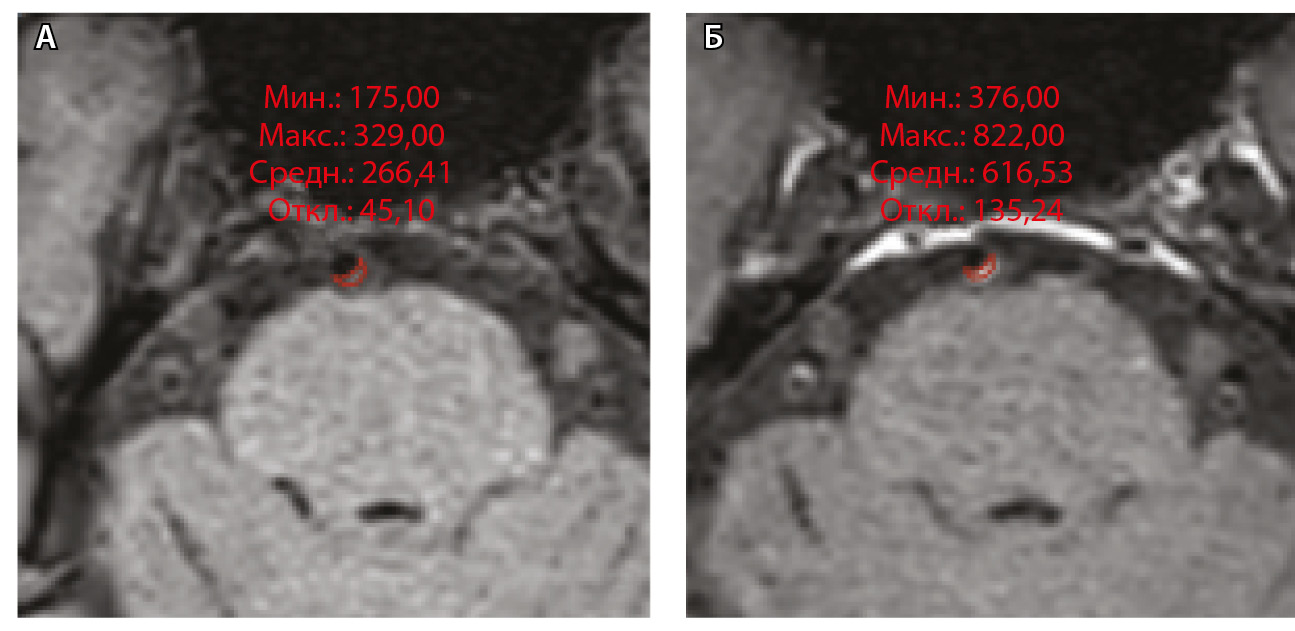

где WEI (wall enhancement index) – индекс усиления контрастности стенки (сосудов), SIwallprecontrast – интенсивность сигнала (Signal Intensity, SI) сосудистой стенки (wall) в зоне интереса на преконтрастных (precontrast) изображениях, SIwallpostcontrast – интенсивность сосудистой стенки в зоне интереса на постконтрастных (postcontrast) изображениях; SIbrainprecontrast – интенсивность неизмененного белого вещества мозга (brain) на доконтрастных изображениях; SIbrainpostcontrast – интенсивность неизмененного белого вещества мозга на постконтрастных изображениях. Пример измерения интенсивности сигнала от АСБ для расчета WEI приведен на рисунке 1.

Рис. 1. Пример измерения интенсивности эхо-сигнала от атеросклеротической бляшки базилярной артерии для расчета индекса усиления контрастности стенки сосуда (WEI). В месте максимального стеноза артерии на одном срезе отмечали область интереса (ROI) и регистрировали среднее значение интенсивности сигнала от сосудистой стенки (SIwall). ROI были сопоставлены по размеру и местоположению в наборе данных T1-TSE-db-FS до (А) и после (Б) контрастного усиления; макс. – максимум, мин. – минимум, откл. – отклонение, средн. – среднее